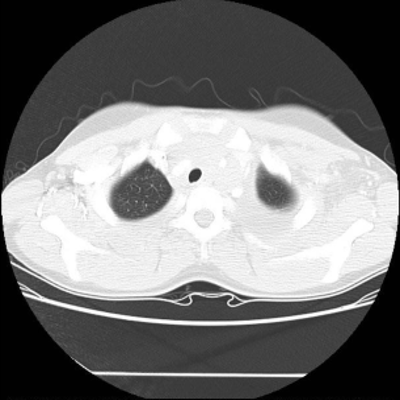

Figure 10. The chest CT example.

7.3. Real CT images

We then test our method on slices of chest CT images obtained from the Open Access Biomedical Image Search Engine [2]. Fig. 10(a) and 10(b) show the source image and target image respectively, and the intensity difference is shown in Fig. 10(c). The registration result obtained by our proposed method is shown in Fig. 10(d) (see also the result with the deformed underlying grid in Fig. 10(e)). From the final intensity difference plot in Fig. 10(f), it is easily to see that our method matches not only the two large components but also the small dot at the center very well. On the contrary, DDemons [47] produces a suboptimal registration result with a significantly larger mismatch of the small component at the center (see Fig. 10(g) and Fig. 10(h)).